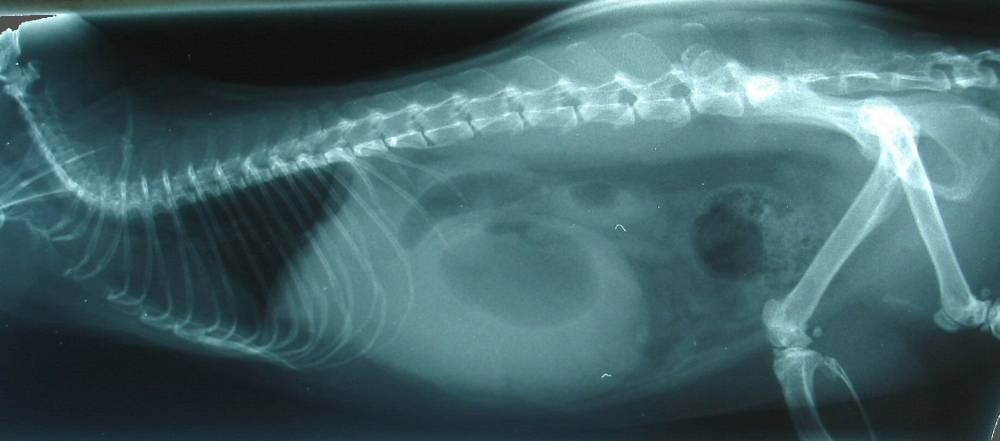

Der Rattenbock bekam zuerst ein starkes Schmerzmittel gespritzt und

wurde dann abgetastet. Dabei fühlte der Tierarzt eine große

weiche

Umfangsvermehrung. Dann wurde er ohne Narkose (war in seinem Zustand

nicht nötig) geröngt.